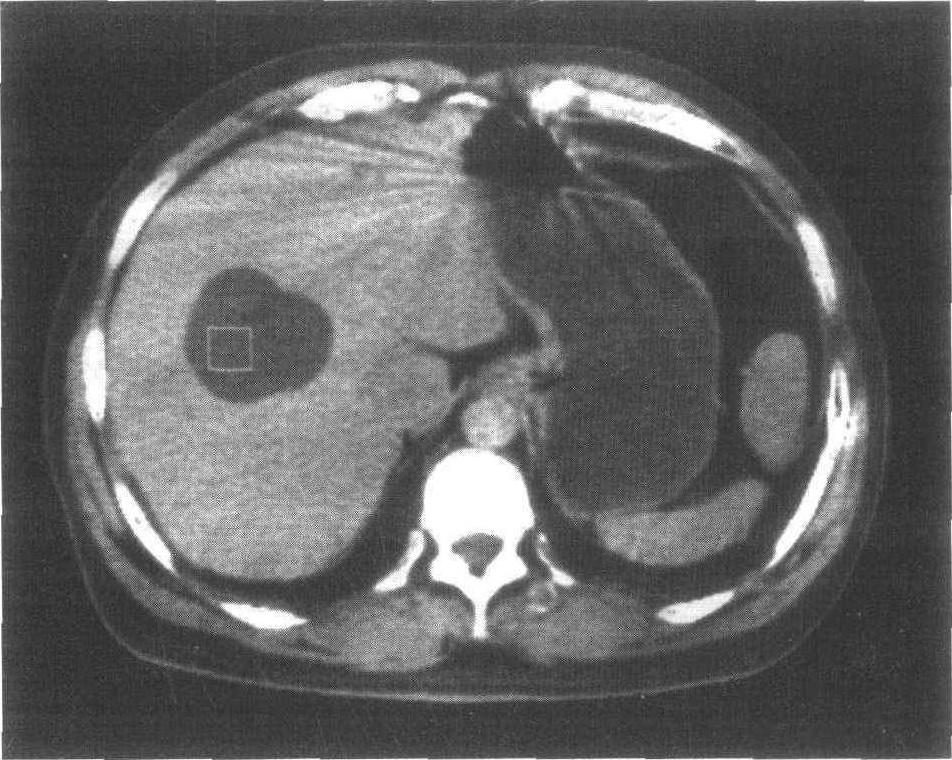

肝脏水泡实际上是一种通俗的说法,在超声波的诊断上是属于肝脏的无回音病灶,呈现在超声波上的标准图像是纯黑色的圆形构造,并且在超声波图像后端出现回音增强的情形,其实就是肝部的囊肿,或者称为肝囊肿。

肝脏出现单纯性囊肿的比例其实并不低,统计认为占了全人口数的3.6%,是一种相当常见的问题,所以当超声波的图像出现这种特征,医师就会推测该病灶为无害的单纯性肝囊肿,在我国某些地方也被俗称为肝脏水泡。

另外,在肝脏出现囊肿的情形,也有可能是转移过来的、会分泌黏液的肿瘤。又或者是因为脂肪干扰了超声波的图像,在这种情形下,肝脏的囊肿就不会是纯黑色的,而是灰黑或淡灰色,跟其他的小型肝肿瘤就无法做区分。所以第一次发现的水泡如果不是太大,医师会建议至少3个月后必须要进行一次复查,以评价该囊肿长大的速度。快速增生的囊肿,或囊肿中可见隔间、小肿瘤的囊肿,要考虑切除或进一步检查。

还有一种情形要注意,是CT扫描时诊断中发现的肝脏囊肿。因为肝脏出现“水泡”实在是太常见了,所以对于CT扫描图像中不显影的病灶,影像学医生一样会认为是属于无害的肝脏囊肿,但实际上,转移到肝脏的肿瘤以及肝脏的淋巴瘤,同样也是不显影或显影不明显的。因此,临床医生对于超声波跟CT扫描影像诊断不一致的情形,还是会要求病人必须复查跟踪监测,或安排其他检查,以便确诊或者排除其他疾病。